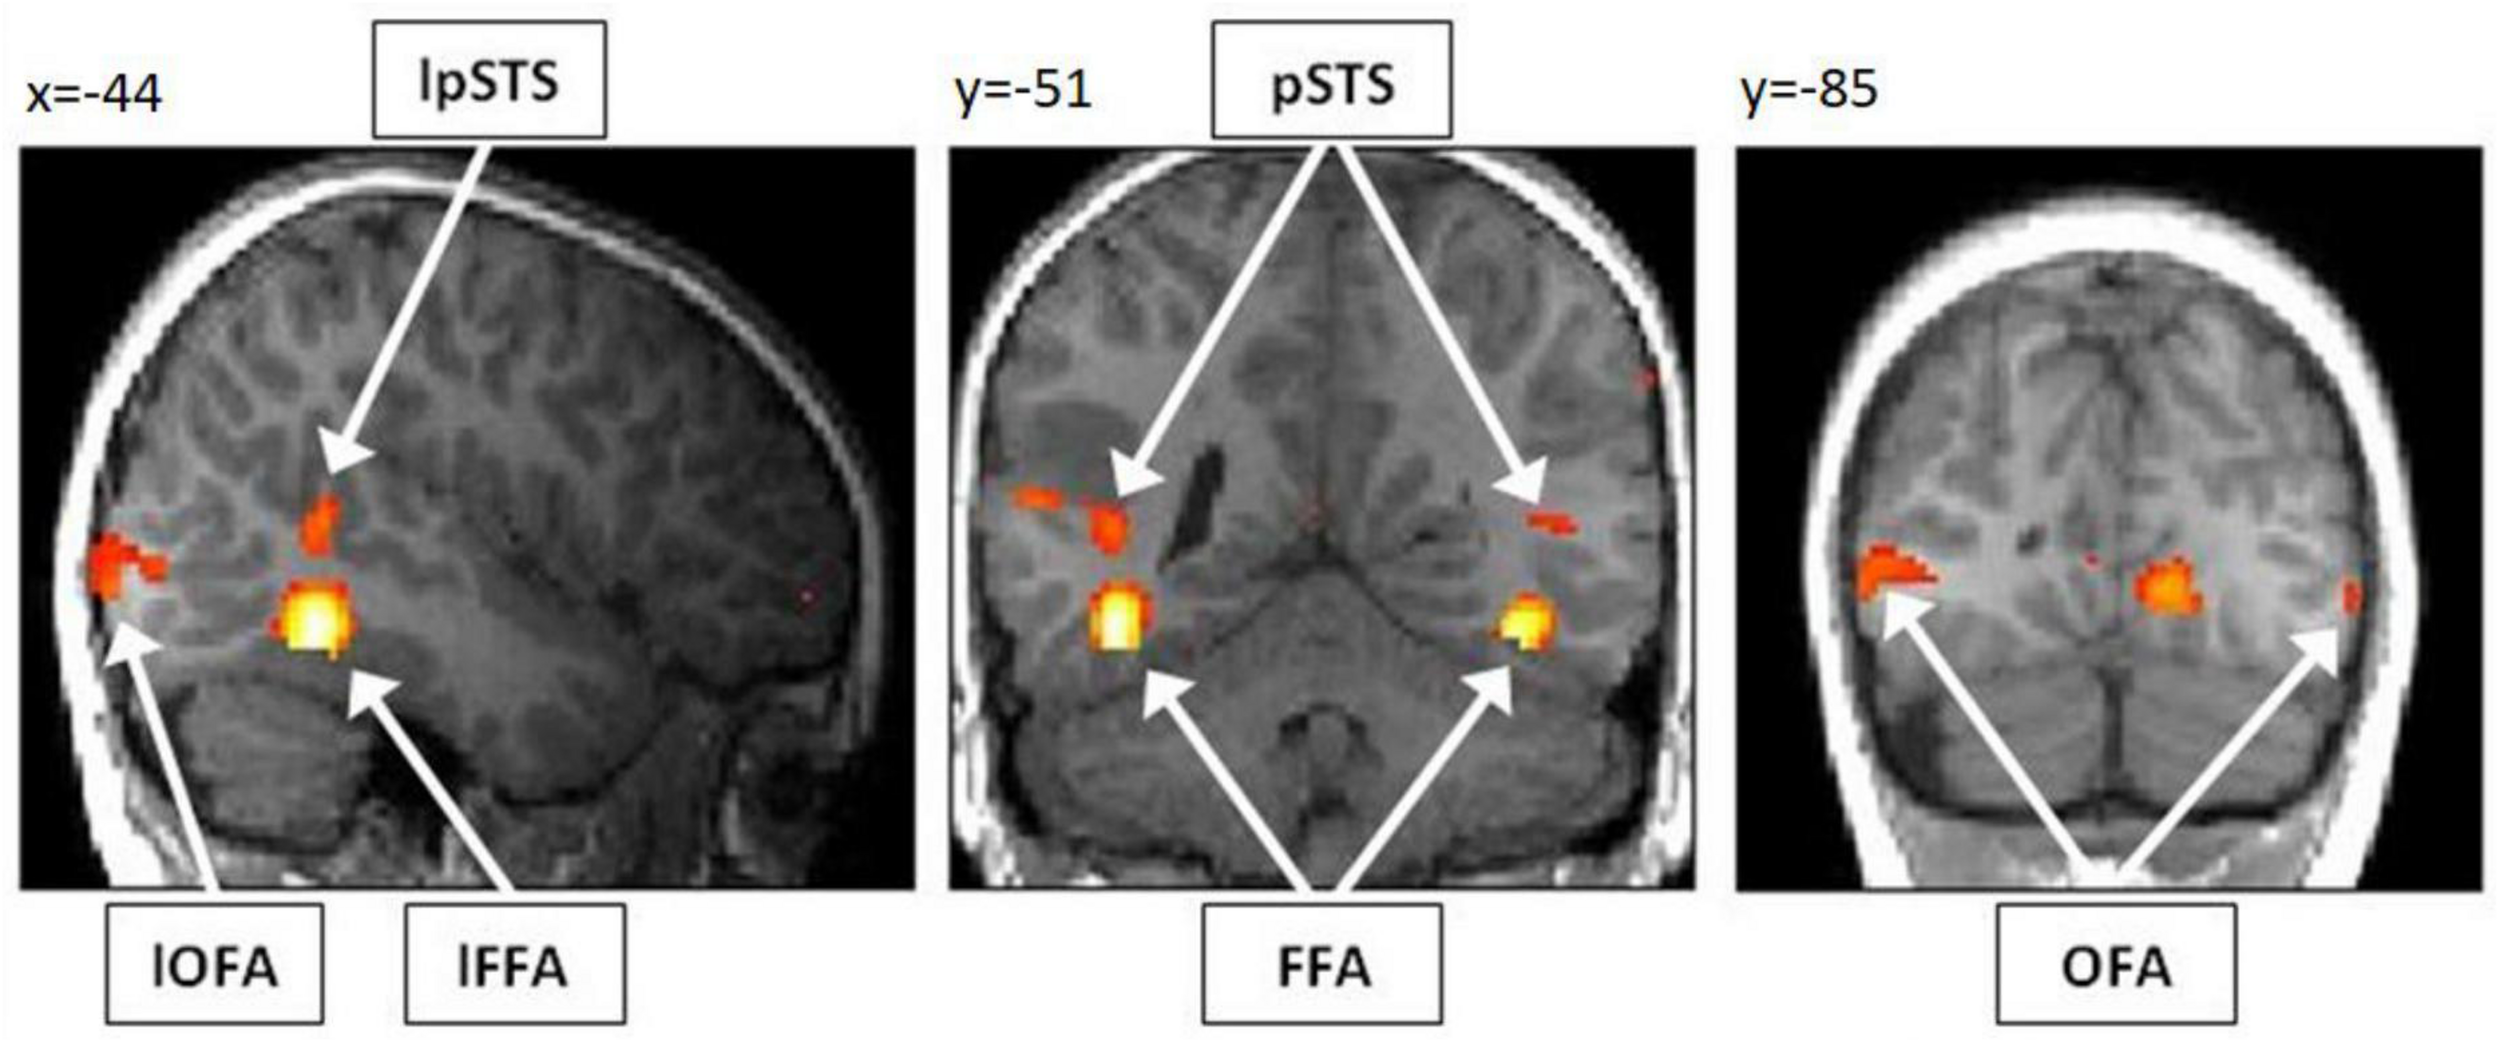

Our first aim was to assess whether it is possible to detect brain activity in the core system of face processing in children at the single subject level. For illustrational purposes, a representative brain activation pattern is shown in Figure 4. At the group level, we found in the adults group clearly discernible face-sensitive brain activity in bilateral OFA and bilateral pSTS (p < 0.001, uncorrected). In the children group, we found brain activity in the right OFA and bilateral pSTS at p < 0.001, uncorrected. The left OFA was activated at p < 0.05, uncorrected. In contrast, the left and right FFA was not activated in both groups, not even at a liberal threshold of p < 0.05, uncorrected (see discussion for an explanation). At the individual subject level, all regions of the core system of face processing could be identified in almost all subjects. In most cases, activity was found even at conservative statistical thresholds, i.e., at p < 0.05, FWE corrected for multiple comparisons at the whole-brain level. These results suggest that the core face processing regions, i.e., bilateral OFA, FFA and pSTS can be portrayed at the single-subject level in children and adults, with 100% ROI identification scores of OFA in both samples and slightly lower ROI identification scores of bilateral FFA and pSTS (see Figure 5 for details).

FIGURE 4

Activation pattern of a representative child (7 years, male) for the contrast “faces > houses.” As overlay T1 image, the normalized and smoothed structural T1 scan of the respective child was used. The subject shows clearly discernible activity in bilateral OFA, FFA and pSTS. For illustrational purposes, the activation pattern is thresholded at p < 0.001, uncorrected for multiple comparisons. Note, however, that all six activations were significant for multiple comparisons (p < 0.05 FWE corrected) at the predefined ROI masks for bilateral OFA, FFA, and pSTS. OFA, occipital face area; FFA, fusiform face area; pSTS, posterior superior temporal sulcus; l, left.